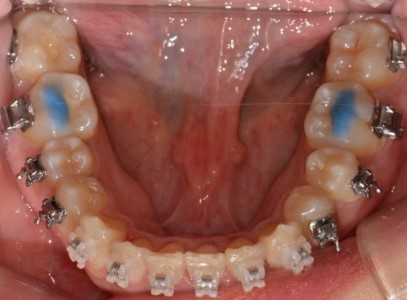

판교교정치과 교정 바이트 블럭(Bite Block) 사용 이유 | 레진 블록 역할·기간·주의사항